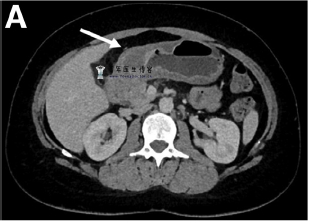

蜂窝织炎性胃炎一例

病例描述 一名健康的41岁女性因上腹疼痛、恶心、呕吐伴发烧4天来就诊。 入院时该患者发热至40.1 C,她的血压、心率和血氧饱和度均正常。而实验室检查结果发现C-反应蛋白达到了190 mg/L(参考范...